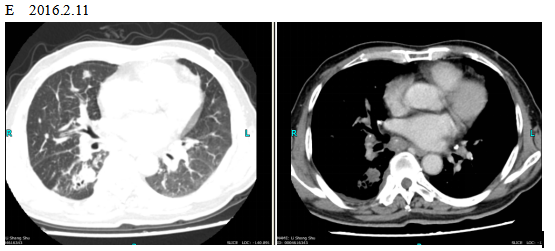

The patient checked for further treatment on November 23, 2015. A pre-chemotherapy assessment was made and the results showed multiple bone metastases and multiple enlarged lymph nodes in the left shoulder blade, the fourth lumbar, the right iliac bone and other locations. Performance status (PS) was only one point. Pemetrexed Disodium (500 mg/m2 d1) + Carboplatin (AUC 5 d1) + Bevacizumab (7.5 mg/Kg d1) was administered beginning November 26, 2015 for the chemotherapy treatment and supportive therapy was provided, such as, dehydration, reduction of intracranial pressure, promotion of bone repair, pain relief, and waist protection. After discharge, the coughing basically disappeared and the dizziness, backaches, and hemiparesthesia of the left side were significantly improved. Patient emotional state and sleep quality was significantly improved. It was basically normal after a routine blood examination. A second chemotherapy treatment was successfully completed on December 18 (the program is idem). The patient returned to the hospital on January 6, 2016 and was proposed for a third chemotherapy. The pre-chemotherapy assessment showed that the measurable, targeted right lung lesion had decreased (3.2 mm, with a rate of decrease 44.8 %) (Fig. 1D). Lymphangitis carcinomatosa was significantly decreased and right frontal nodulus lesions were reduced significantly (Fig. 2C). No new lesions were found. Efficacy was assessed as partial relief (PR). A third and fourth chemotherapies were completed on January 9 and January 30, 2016. Efficacy was re-assessed as PR (Fig. 1E) with lung CT review as an outpatient on February 11. Since then, the patient had been subjected to a combined administration program of pemetrexed disodium (500 mg/m2 d1) + bevacizumab (7.5 mg/Kg d1) for continued chemotherapy. A lung CT and a cranial MRI were peformed on April 16. The results showed that the control of lung lesions and intracranial lesions were basically the same as before (Fig.1F and Fig. 2D). The patient had no cough, backaches, or hemiparesthesia and the quality life significantly improved. PS was decreased to zero.